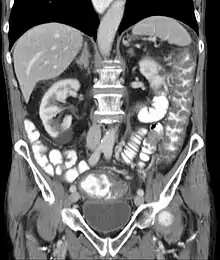

| Pathological specimen showing pseudomembranous colitis | |

Prior to the advent of tests to detect C. difficile toxins, the diagnosis most often was made by colonoscopy or sigmoidoscopy. The appearance of "pseudomembranes" on the mucosa of the colon or rectum is highly suggestive, but not diagnostic of the condition.[45] The pseudomembranes are composed of an exudate made of inflammatory debris, white blood cells. Although colonoscopy and sigmoidoscopy are still employed, now stool testing for the presence of C. difficile toxins is frequently the first-line diagnostic approach. Usually, only two toxins are tested for—toxin A and toxin B—but the organism produces several others. This test is not 100% accurate, with a considerable false-negative rate even with repeat testing.[46]

The use of systemic antibiotics, including broad-spectrum penicillins/cephalosporins, fluoroquinolones, and clindamycin, causes the normal microbiota of the bowel to be altered. In particular, when the antibiotic kills off other competing bacteria in the intestine, any bacteria remaining will have less competition for space and nutrients. The net effect is to permit more extensive growth than normal of certain bacteria. C. difficile is one such type of bacterium. In addition to proliferating in the bowel, C. difficile also produces toxins. Without either toxin A or toxin B, C. difficile may colonize the gut, but is unlikely to cause pseudomembranous colitis.[44] The colitis associated with severe infection is part of an inflammatory reaction, with the "pseudomembrane" formed by a viscous collection of inflammatory cells, fibrin, and necrotic cells.[20]